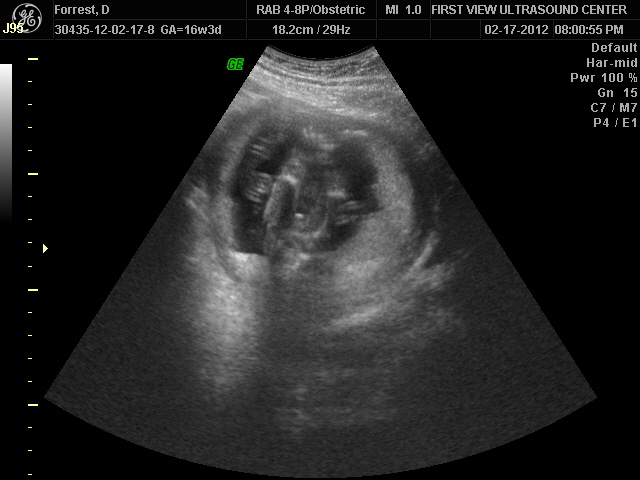

On Thursday we went to the doctor for your 20 week ultrasound. Normally this is when people find out what they are having but we were there to measure all of you, make sure nothing is wrong, and confirm you are still a boy. Nana and Papa came with Daddy and me. I was excited for them to see you!

You are definitely still a boy, and proud of it! When we went in the person doing the ultrasound informed me I have two placentas. This could explain why I don't feel you yet. I looked online to see about this and for some people it means there was a twin that did not make it. I don't think that is what happened since they have always only heard your heart beat and not another one. It could just be a freak thing. It is good to know! You are symmetrical, your heart looks good, you have two arms and two legs, two kidneys, and everything else looks good. Here are some pictures of you!

Your two arms: